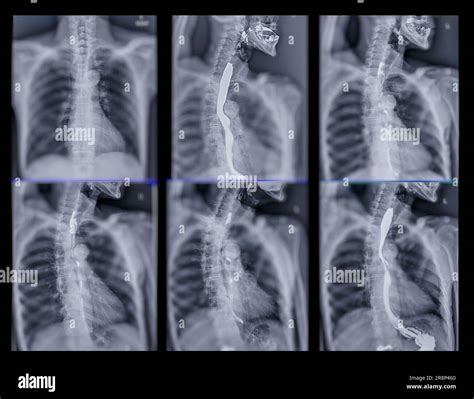

A Video Swallow Study, also known as a modified barium swallow study, is a diagnostic procedure that uses fluoroscopy to observe the swallowing process in real-time. During the study, the patient ingests barium-coated food or liquid, which makes the swallowing structures visible on X-ray images. This allows healthcare professionals to identify any abnormalities or obstructions in the swallowing pathway.

1. Patient Positioning: The patient is positioned in front of a fluoroscopy machine, which captures real-time X-ray images.

2. Barium Administration: The patient is given barium-coated food or liquid to swallow. The barium makes the swallowing structures visible on the X-ray.

3. Swallowing Observation: The healthcare provider observes the swallowing process on a monitor, noting any abnormalities or obstructions.

4. Data Collection: The fluoroscopy images are recorded for detailed analysis and documentation.

Interpreting the results of a Video Swallow Study involves analyzing the fluoroscopy images to identify any abnormalities in the swallowing process. Key areas of focus include:

• Pharyngeal Phase: The movement of the bolus (food or liquid) through the pharynx and the coordination of the pharyngeal muscles.

• Esophageal Phase: The movement of the bolus through the esophagus and into the stomach.